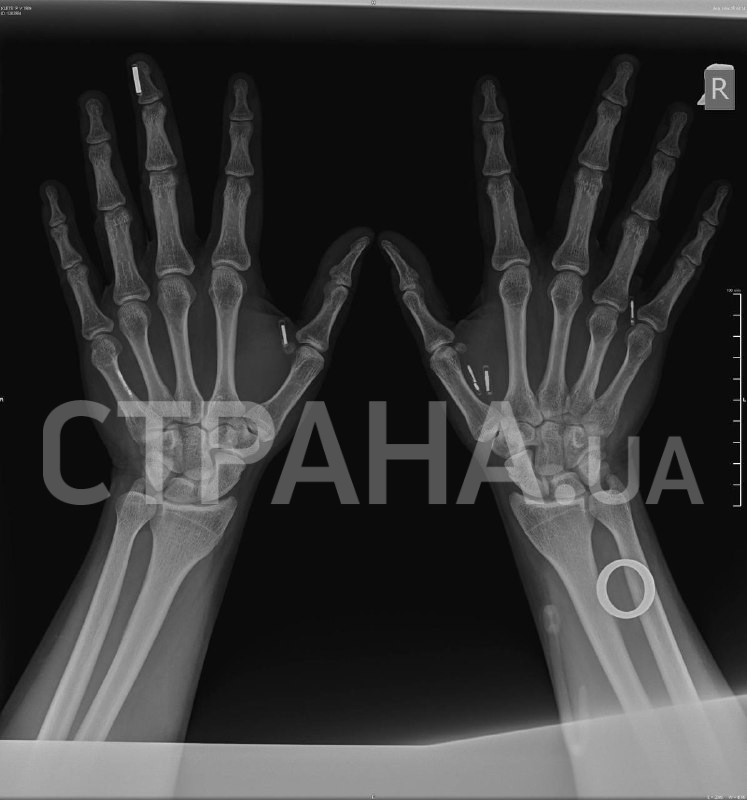

Восемь миниатюрных чипов в руках Клеца позволяют расплачиваться за покупки, заводить авто и многое другое, не пользуясь дополнительными гаджетами.

– Когда я ехал на пресс-брифинг, где мне вживили восьмой чип, очень переживал, что столкнусь со шквалом критики, что меня будут поджидать какие-то фанатики, чтобы напасть на меня или еще что-то. Но реакция была совсем иной, я, честно, даже не ожидал, что все к этому отнесутся с пониманием и интересом. Дело в том, что имплантаты, электронные или нет, давно существуют в нашей жизни: люди ставят себе зубы, ремонтируют кости. Вы же не отказываетесь от гипса, потому что он надевается на руку. Люди не отказываются от спиц в руке, хотя это то же самое, что вживить чип. Я не до конца понимаю, в чем разница между имплантируемой электроникой и любым другим имплантом, но все равно уважаю мнение этих людей, пусть оно будет.

– У меня есть чипы и магниты. С чипами вообще все просто: более десяти лет назад в передаче "Разрушители мифов", ещё тогда чипы более простой конструкции проверяли на то, влияет ли на них аппарат МРТ. Нет, он не влияет, функциональность сохраняется, человек этого даже не ощущает.

– Иными словами, у вас в руке сейчас находится платежное кольцо, которое предназначено для внешнего ношения на пальце и оплаты им по платежному терминалу?

– Совершенно верно. Его нужно было правильно стерилизовать для интеграции под кожу. Находясь в стерильном пакете и пройдя все процедуры, оно продолжило быть рабочим устройством. То есть устройство, которое было сделано для ношения на пальце. Нам оставалось только взять и попробовать. Мы взяли и попробовали, я два месяца им пользуюсь, все работает, все круто.